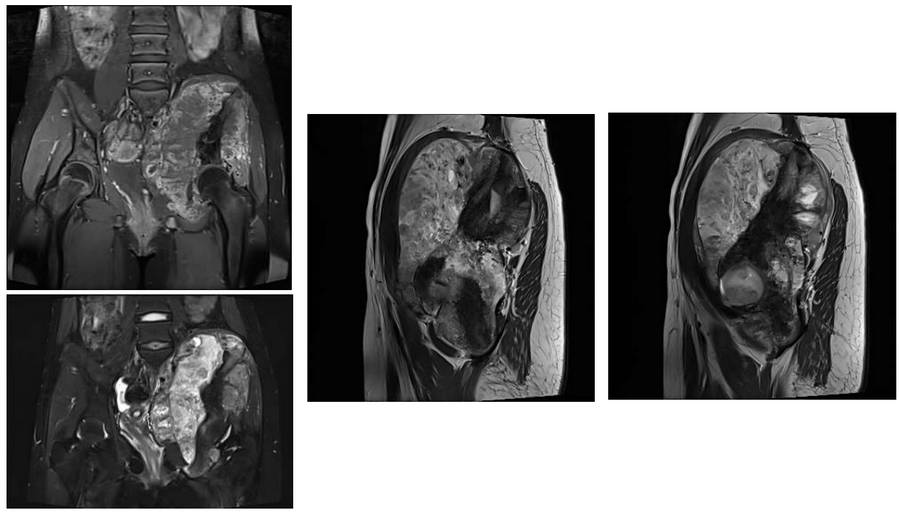

Before the surgery: The MRI shows a large tumor tissue that has caused bone destruction affecting the entire 5th lumbar vertebra, sacrum, and iliac crest, and extending into the soft tissue.